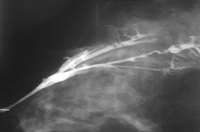

Avaliação de massa mamária

Ductografia demonstrando papilomas intraductais múltiplos

Cortesia da Dra. Nancy Pile, Universidade de Louisville; usado com permissão